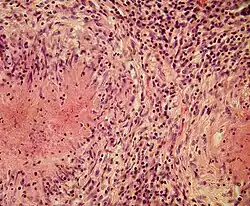

Structurally, epithelioid cells (when examined by light microscopy after stained with hematoxylin and eosin), are elongated, with finely granular, pale eosinophilic (pink) cytoplasm, and central, ovoid nuclei (oval or elongate), which are less dense than that of a lymphocyte.[4] They have indistinct shape and often appear to merge into one another, forming aggregates known as giant cells. When examined by transmission electron microscopy in epithelioid cells in the field of Golgi lamellar complex are taped not only zonated, but also sleek vesicles with dense center, and also great many (more than 100) large granulas with diameters up to 340 nm and with finegranular matrix more light than in macrophage granulas, sometimes with perigranular halo. “The most prominent feature of these cells is the enormous Golgi area; up to 6 individual stacks of Golgi cisternae may be present as well as a few bristle-coated and numerous smooth vesicles”.[5][4] Epithelioid cells have tightly interdigitated cell membranes in zipper-like arrays that link adjacent cells.[3] This cells are central in the formation of granulomas, which are associated with many serious diseases.[4] In granulomas, epithelioid cells perform the functions of delimiting.[3]